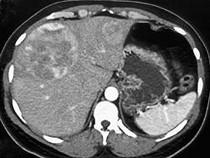

女,65岁,肝区疼痛1月余,CT检查如图,最可能的诊断是()A.原发性肝癌B.类癌转移至肝C.肝腺瘤D.肝血管瘤E.肝错构瘤

问题 女,65岁,肝区疼痛1月余,CT检查如图,最可能的诊断是()

选项 A.原发性肝癌 B.类癌转移至肝 C.肝腺瘤 D.肝血管瘤 E.肝错构瘤

答案 B